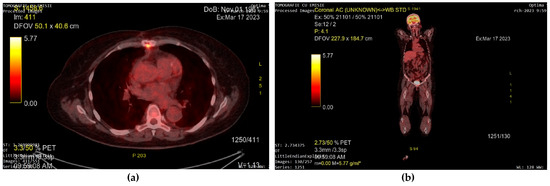

A transthoracic echocardiography (TTE) was performed. It showed a round 25/30 mm, 6.5 cm2 intracardiac mass attached to the right ventricle outflow tract (RVOT) wall by a 5 mm thick pedunculus (Figure 1a), which prolabated through the pulmonary valve in systole, thus causing severe obstruction at this level with a maximum gradient of 70 mmHg (Figure 1b and Figure 2). The pulmonary valve itself presented no structural abnormalities, but the right ventricle was dilated (50 mm at the base) with a slightly decreased systolic function (TAPSE = 15 mm), a moderate tricuspid regurgitation and paradoxical interventricular septum motion being also observed due to right ventricular pressure overload. The left ventricle was not dilated and had a preserved systolic function, and only a mild mitral regurgitation was noted.

Figure 1. Transthoracic echocardiography (TTE) showing: (a) a round intracardiac mass attached to the right ventricle outflow tract (RVOT) wall by a pedunculus (white arrow); (b) turbulent flow on Color Doppler caused by the tumor’s severe obstruction of the RVOT (white arrow).